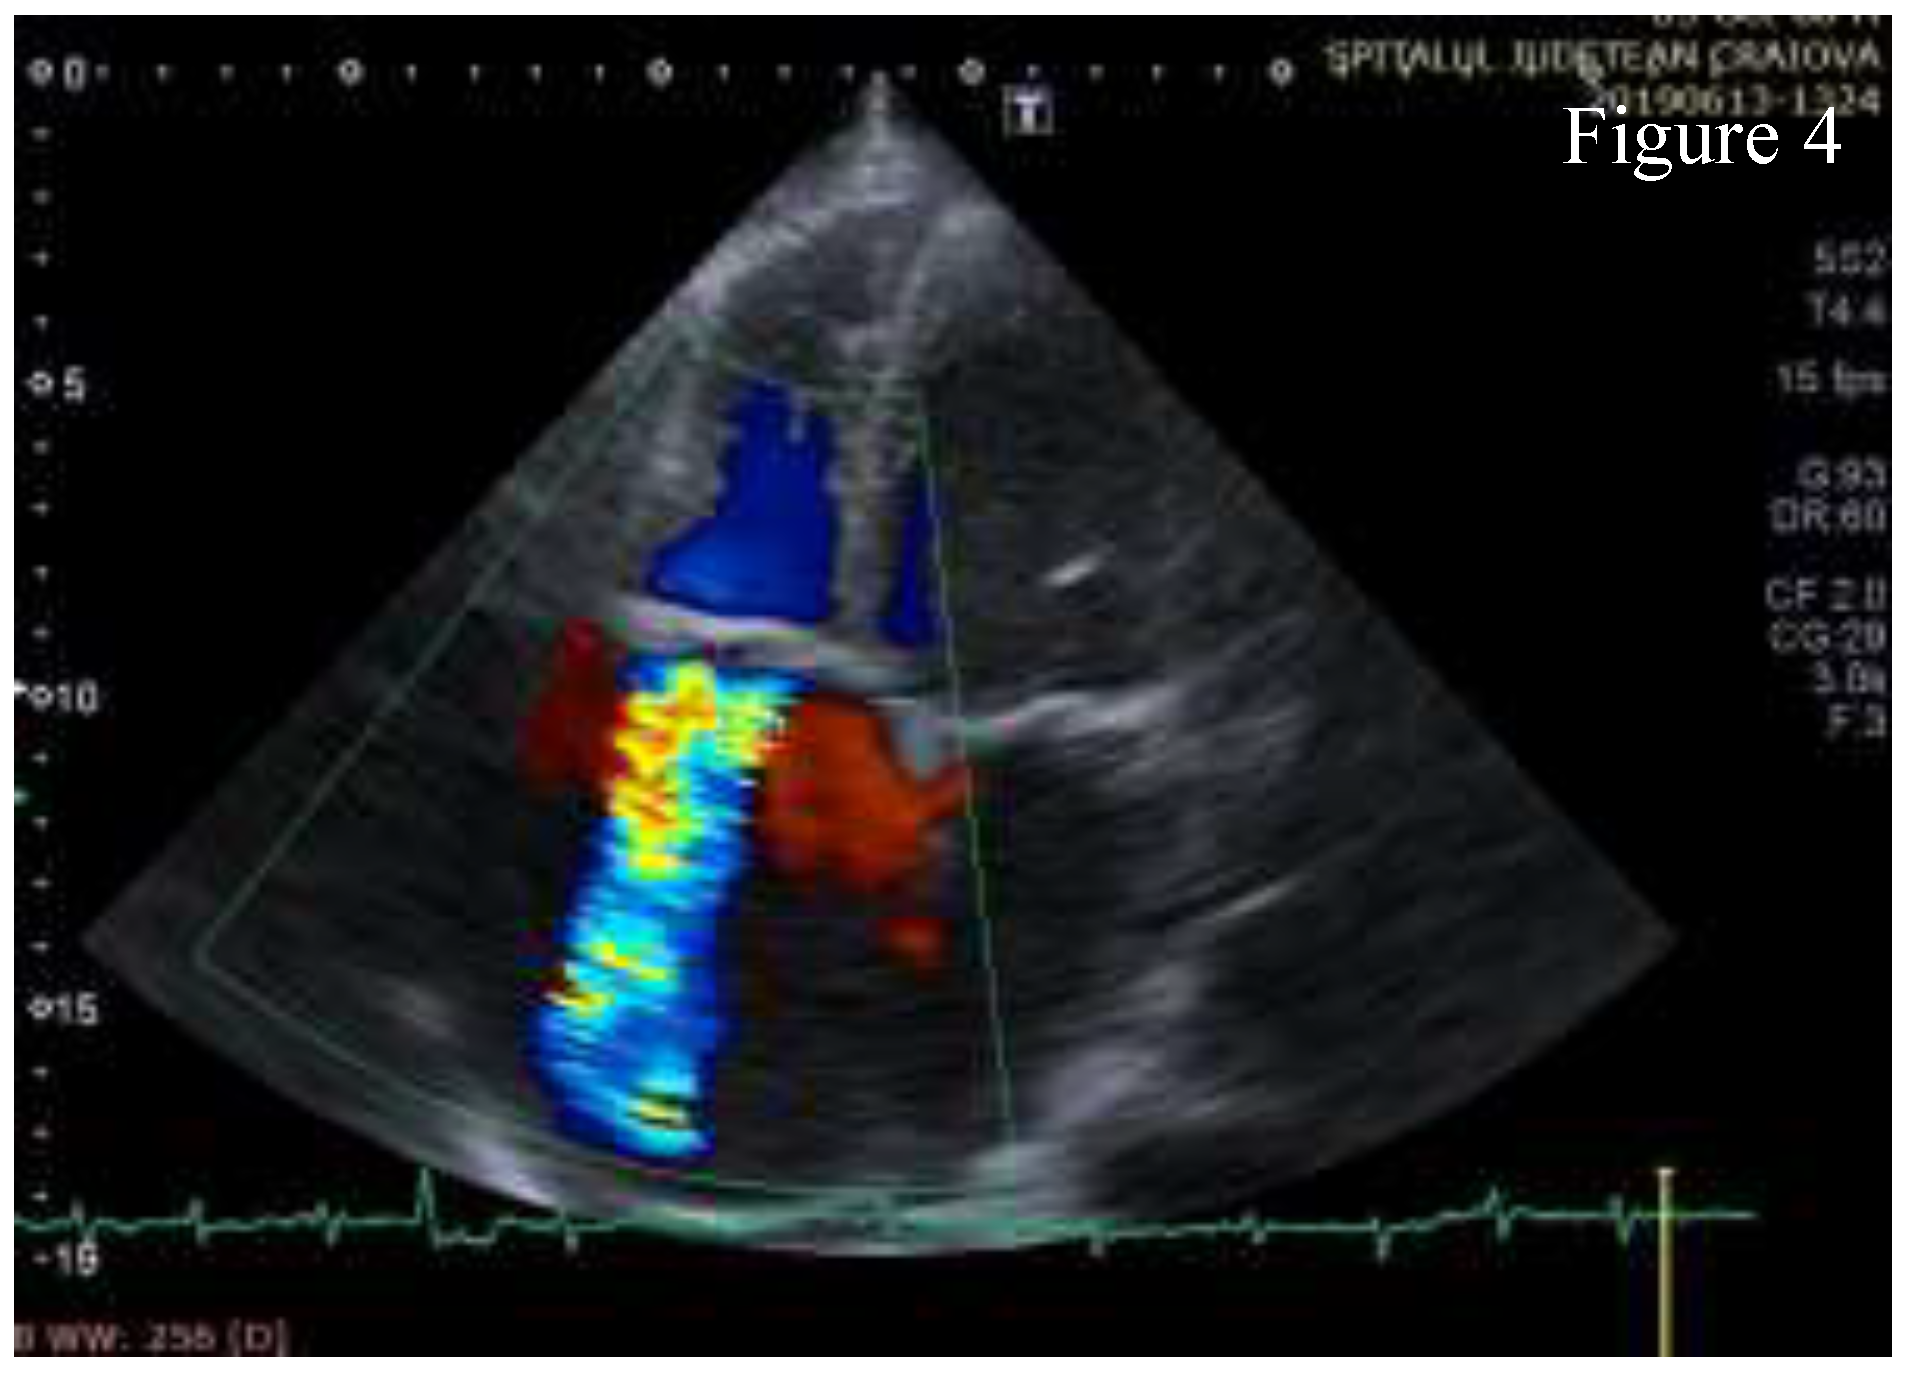

Transthoracic echocardiography (TTE) showed significant structural changes in the tricuspid valve. Anterior and posterior cusps were thickened, calcified, and had restricted motion. Subvalvular chords were thickened. Structural changes caused severe regurgitation (effective regurgitant orifice area= 0.57 cm2, regurgitant volume= 45 ml) and moderate stenosis (high diastolic gradient of 13/6 mmHg which contributed to the high inflow accompanying severe regurgitation). Right chambers were dilated with right ventricle longitudinal systolic dysfunction (TAPSE= 16mm, S’value = 10 cm/s) and with dilated inferior vena cava indicating increased pressure in the right atrium. These aspects are shown in Figure 1, Figure 2, Figure 3, Figure 4, Figure 5.

Figure 4.

A4C Color Doppler - severe tricuspid regurgitation.